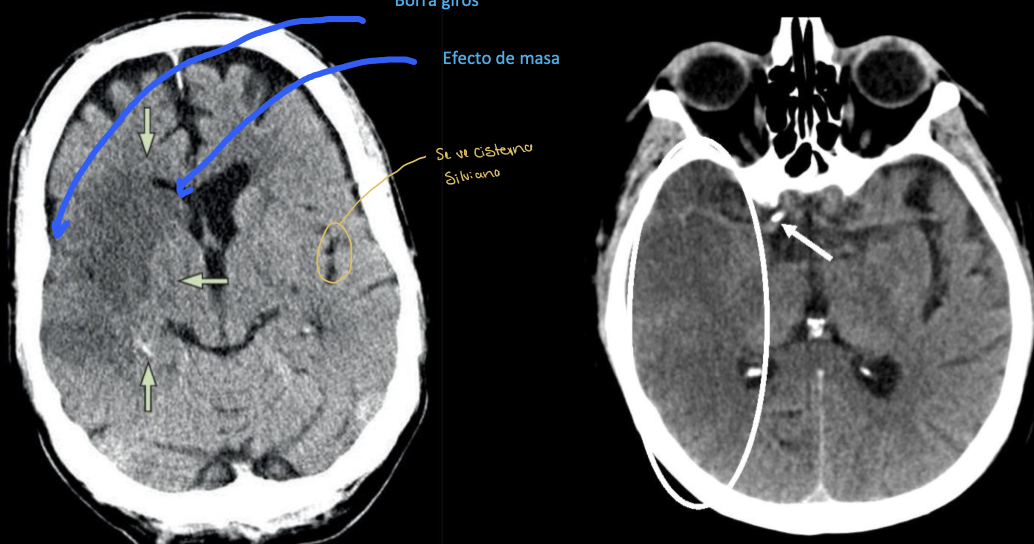

16

Q

Diagnóstico:

A

EVC isquémico en fase aguda